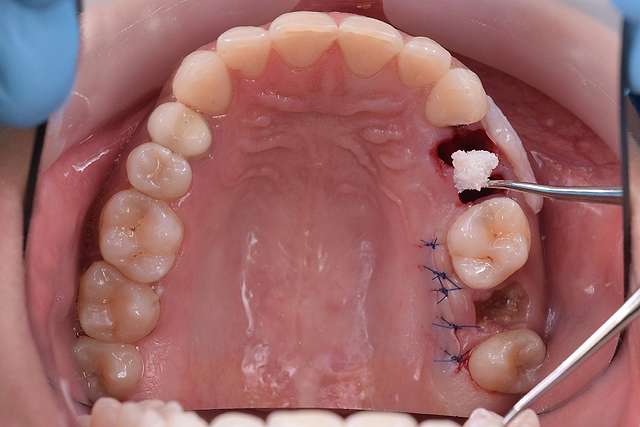

Chirurgia ghidata, ne faciliteaza o pozitie ideal pre-planificata, care nu tine cont doar de os, ci si de o pozitie optima in relatie cu viitorul dinte.Chirurgia ghidata înseamnă o precizie crescuta, care inseamna siguranta mai mare, timp operator mai scazut, si trauma mai mica. De asemenea focusul in acest tip de interventii a migrat spre reconstructia tesuturilor, care e pe termen lung are un impact mult mai mare atat estetic cat si biologic, inserarea implantului in sine fiind trivializata de folosirea ghidului chirurgical. Cazul de fata este un exemplu al acestui tip de abordare.